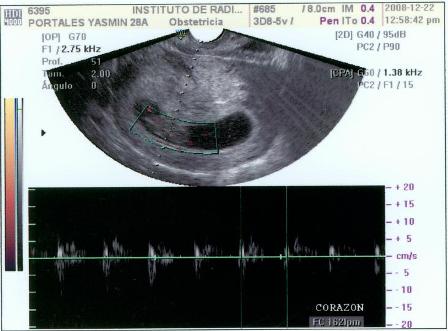

Fotos del 22 Dc 2008:

Informe:

Embrión correspondiente a 9 s cumplidas de embarazo y con FC (frecuencia cardiaca, supongo) de 162 LPM.

Saco gestacional bien conformado y localizado en fondo uterino.

Estructura uniforme de útero con cuello cerrado, ausencia de signos de sangrado gestacional.